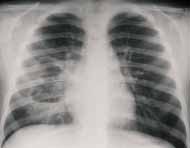

Las neumonías bacterianas ocurren en asociación con inhalación de estos agentes infecciosos dentro el espacio aéreo, lo cual conlleva al desarrollo de edema inflamatorio y exudado en los acinos, causando consolidación de los espacios aéreos. En las radiografías de tórax las consolidaciones se manifiestan como imágenes densas, de distribución lobar o segmentaria. El broncograma aéreo aun cuando no siempre visible, es característico. (Figura 7).

FIGURA 7. Proyección AP de tórax con consolidación neumónica del lóbulo

superior derecho con imagen típica de broncograma en su interior.